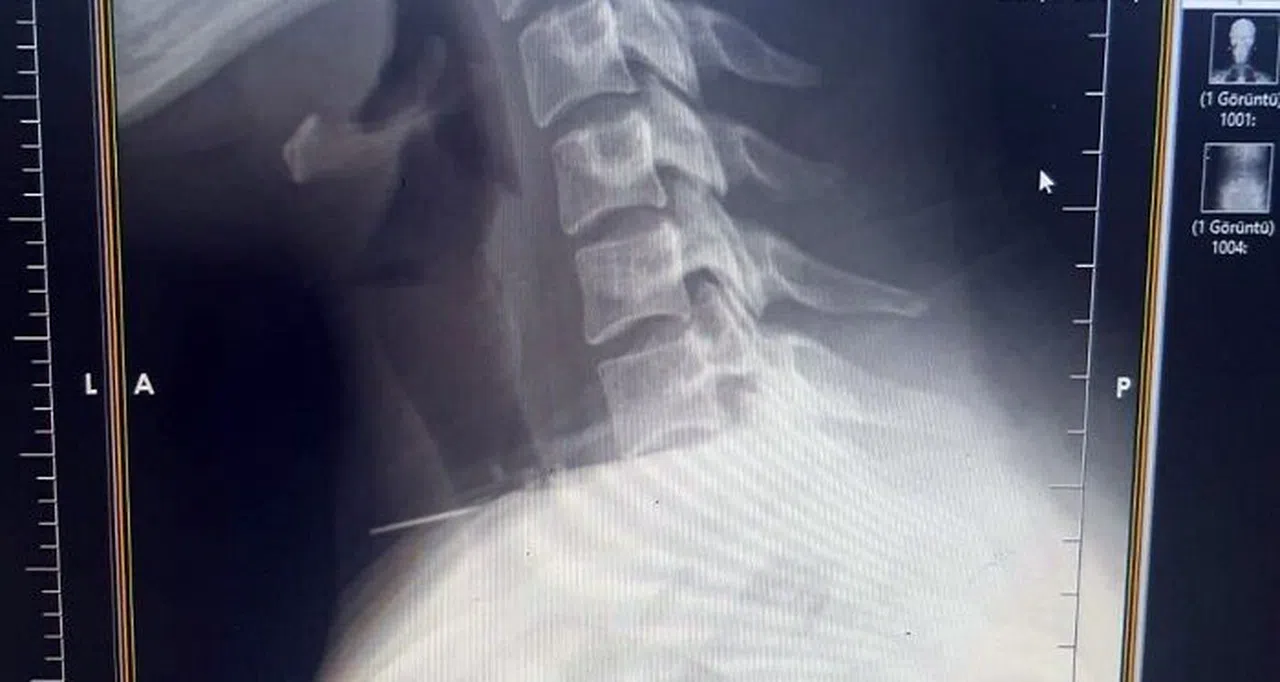

Edinilen bilgiye göre olay, Şanlıurfa’nın Birecik ilçesinde yaşandı. Boğazına dikiş iğnesi saplanan 25 yaşındaki Z.İ., Birecik Devlet Hastanesine başvurdu. Radyolojik incelemeler ve klinik değerlendirmeler sonucunda, 3 santimetrelik iğnenin boğaz bölgesinin derinliklerine doğru ilerlediği tespit edildi. İğne, yaklaşık 1 saat süren ameliyatla çıkarıldı. Ameliyat sonrası süreci sorunsuz atlatan hasta taburcu edildi. Ameliyatı gerçekleştiren Birecik Devlet Hastanesi Kulak Burun Boğaz ve Baş Boyun Cerrahisi Uzmanı Dr. Rafet Yıldırım, boynuna iğne saplanan kadın hastayı başarılı bir operasyonla sağlığına kavuşturduklarını söyledi.

Şanlıurfa’nın Birecik ilçesinde bir kadının boğazına saplanan iğne, ameliyatla çıkarıldı.